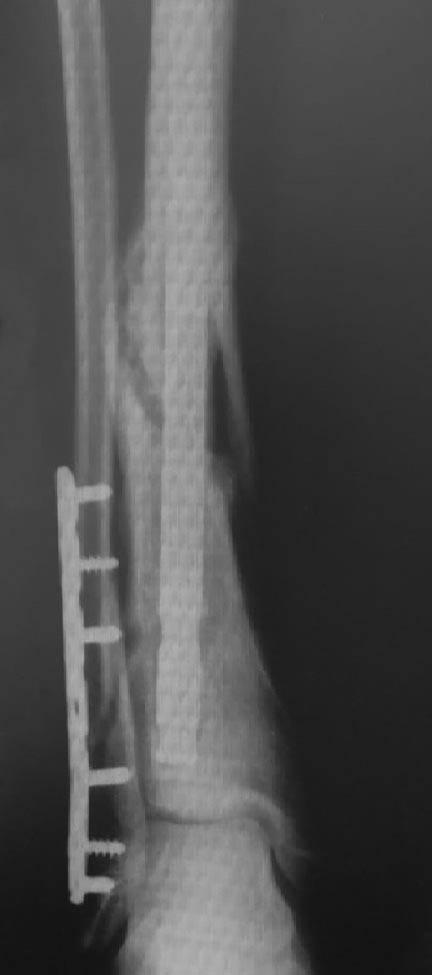

Замедленная консолидация ББК

Молодой пациент 30 лет, 5 мес. назад прооперирован по поводу открытого

перелома (2 ст) большеберцовой кости (стержень), малоберцовой кости

(пластина). В течение указанного времени удален проксимальный

статический винт, удален один дистальный винт в виду его миграции.

Местные ткани - без проблем.